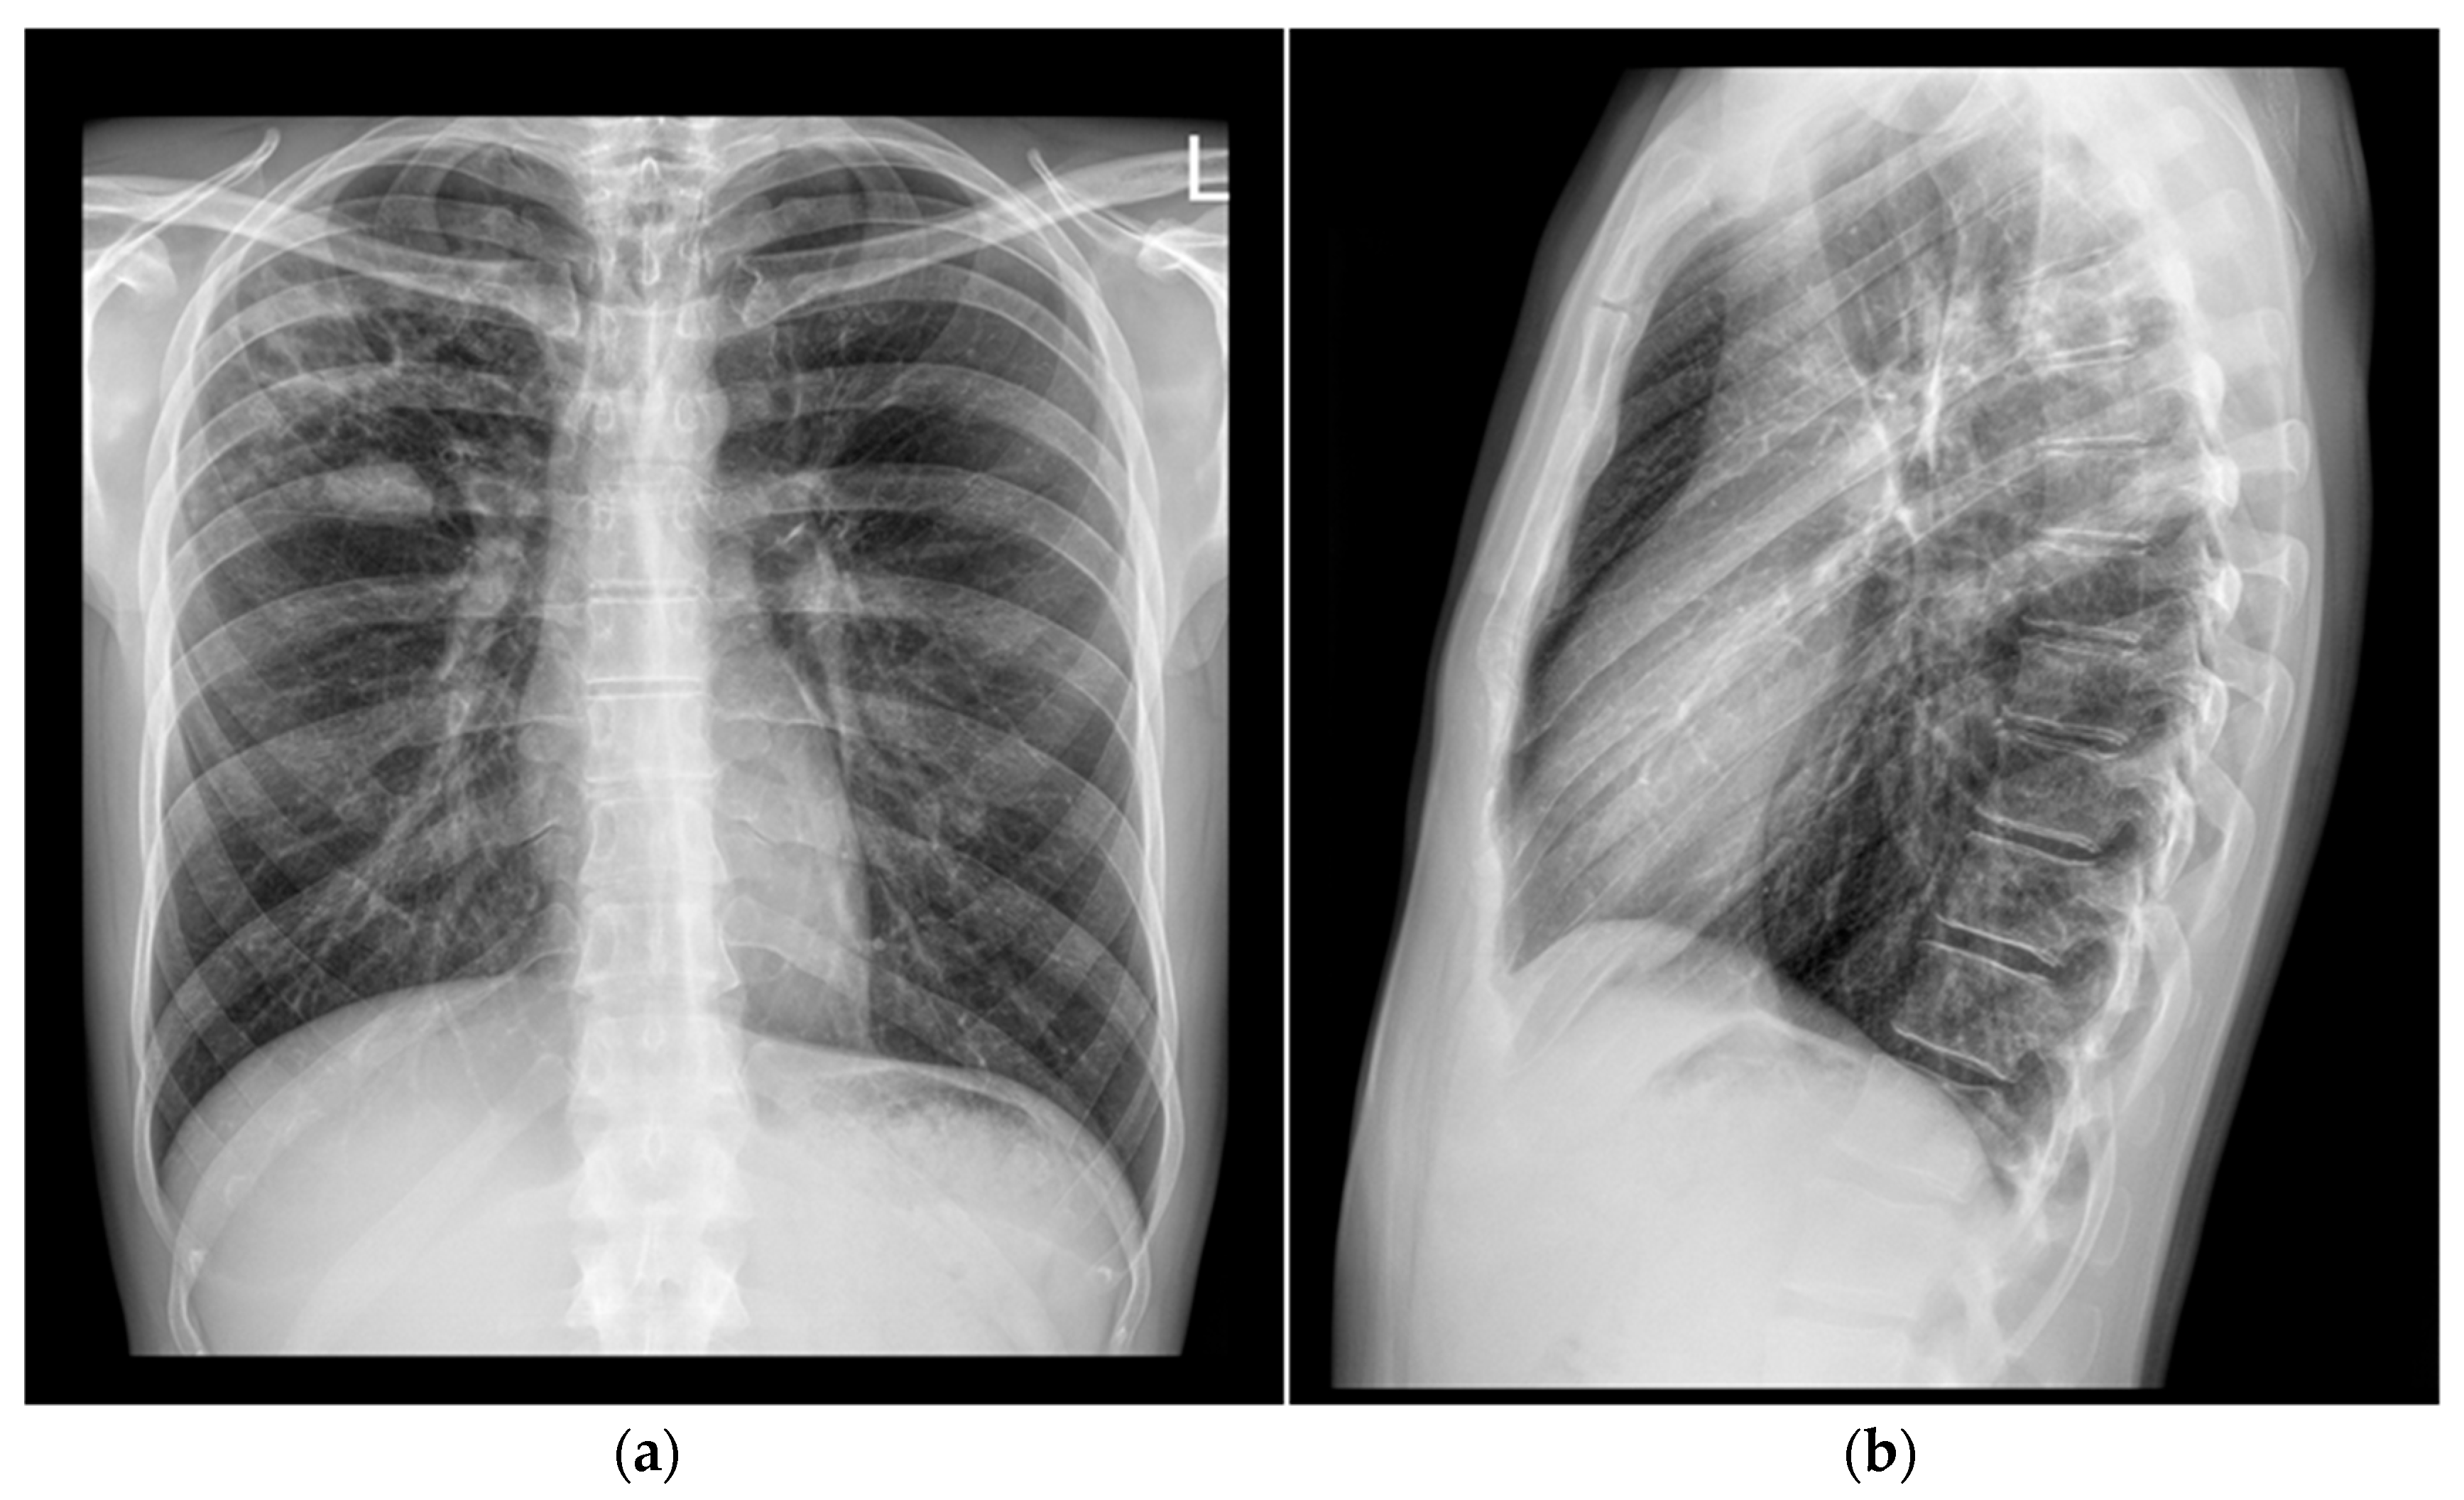

A 37-year-old man was admitted to the Division of Pulmonology, Department of Internal Medicine, Sestre milosrdnice University Hospital Center, on 25 April 2024 due to a two-month history of subfebrile temperature, malaise, productive cough, and night sweats. During the same period, he had experienced loss of appetite and an unintentional weight loss of 4 kg (BMI: 21 kg/m2). The patient had no known chronic medical conditions. He reported occasional cigarette smoking and denied alcohol or illicit drug use. Notably, he had no contact with a known TB patient but reported that his dog had died of disseminated TB six years prior. Based on the patient’s symptoms and a chest X-ray showing features suggestive of a lung abscess in the right upper lobe, his general practitioner initiated empirical antibiotic therapy with amoxicillin/clavulanate (1000 mg t.i.d.) for seven days and referred him to a pulmonologist for further evaluation (Figure 1).

Figure 1. Chest X-rays (25 April 2024). In the upper lobe of the right lung, an area of inhomogeneous opacity is observed, containing a cavity measuring 27 mm in diameter. Additionally, there are fibroadhesive and reticulonodular opacities, along with a larger soft tissue mass exhibiting nodular characteristics: (a) frontal presentation; (b) lateral presentation.